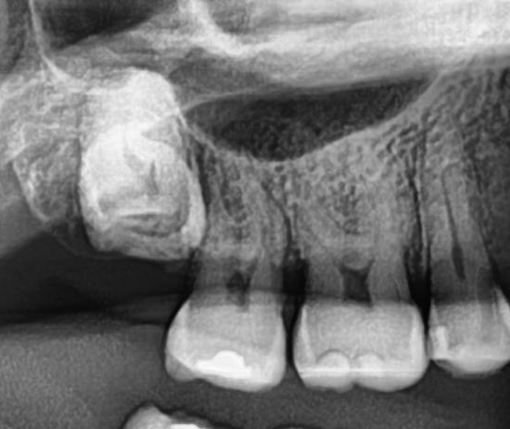

Sometimes, wisdom teeth get stuck in the bone or gums and never fully erupt. These teeth are called impacted teeth. A wisdom tooth extraction in NYC isn’t always required for impacted teeth, but it is advisable if they cause issues.